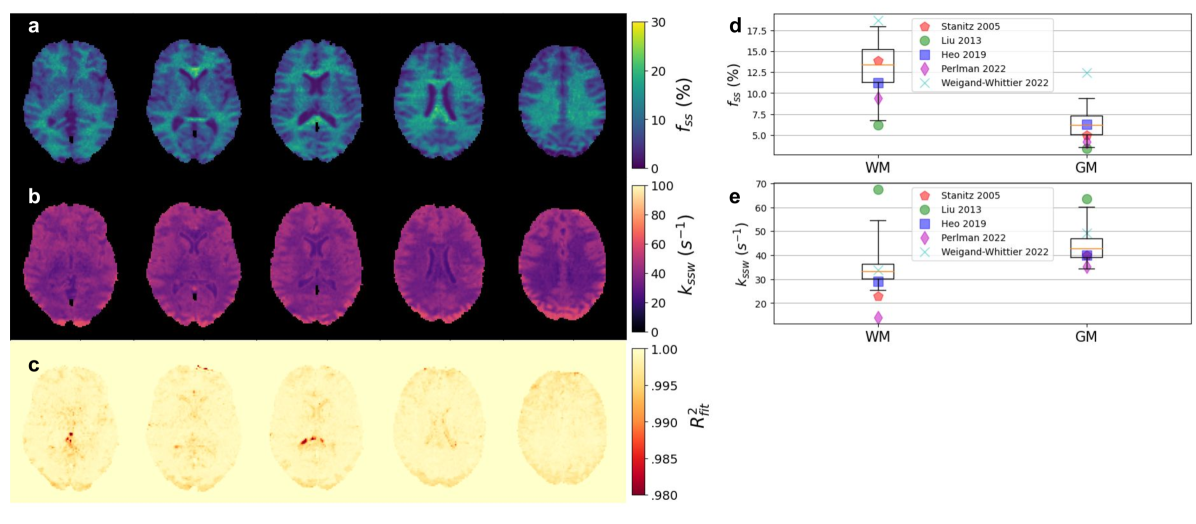

Figure 3: NBMF-based quantification of the semisolid MT proton exchange parameters in the healthy in-vivo human brain. (a-c) Representative reconstructed parameter maps of the semisolid-MT proton volume fraction (a) and exchange rate (b), alongside a fidelity estimation (c) of the data-model agreement, computed as R2superscript𝑅2R^{2}italic_R start_POSTSUPERSCRIPT 2 end_POSTSUPERSCRIPT=1-NMSE (normalized mean square error). (d-e) Statistical analysis of the resulting proton exchange parameter values across the brain white matter and gray matter (WM/GM) regions of interest (box-plots, n=47K/65K), compared to literature (colored markers)[46, 47, 48, 12, 49].

Quantitative semisolid-MT and amide proton exchange parameter maps derived from a representative healthy volunteer are presented in Fig. 3 and Fig. 4, respectively. The resulting proton volume fractions and exchange rates were in agreement with the literature (although the large variability in previous reports is noted; see Fig. 3d-e and Fig. 4d-e). The mean values obtained for white/gray matter (WM/GM) were: fss=13.09±3.44(%),kssw=34.7±7.8(s1),fs=0.33±0.08(%),ksw=305.1±34.0(s1)f_{ss}=13.09\pm 3.44\ (\%),\ k_{ssw}=34.7\pm 7.8\ (s^{-1}),\ f_{s}=0.33\pm 0.0% 8\ (\%),\ k_{sw}=305.1\pm 34.0\ (s^{-1})italic_f start_POSTSUBSCRIPT italic_s italic_s end_POSTSUBSCRIPT = 13.09 ± 3.44 ( % ) , italic_k start_POSTSUBSCRIPT italic_s italic_s italic_w end_POSTSUBSCRIPT = 34.7 ± 7.8 ( italic_s start_POSTSUPERSCRIPT - 1 end_POSTSUPERSCRIPT ) , italic_f start_POSTSUBSCRIPT italic_s end_POSTSUBSCRIPT = 0.33 ± 0.08 ( % ) , italic_k start_POSTSUBSCRIPT italic_s italic_w end_POSTSUBSCRIPT = 305.1 ± 34.0 ( italic_s start_POSTSUPERSCRIPT - 1 end_POSTSUPERSCRIPT ) for white matter and fss=6.28±1.88(%),kssw=44.2±7.5(s1),fs=0.21±0.06(%),ksw=235.9±46.0(s1)f_{ss}=6.28\pm 1.88\ (\%),\ k_{ssw}=44.2\pm 7.5\ (s^{-1}),\ f_{s}=0.21\pm 0.06% \ (\%),\ k_{sw}=235.9\pm 46.0\ (s^{-1})italic_f start_POSTSUBSCRIPT italic_s italic_s end_POSTSUBSCRIPT = 6.28 ± 1.88 ( % ) , italic_k start_POSTSUBSCRIPT italic_s italic_s italic_w end_POSTSUBSCRIPT = 44.2 ± 7.5 ( italic_s start_POSTSUPERSCRIPT - 1 end_POSTSUPERSCRIPT ) , italic_f start_POSTSUBSCRIPT italic_s end_POSTSUBSCRIPT = 0.21 ± 0.06 ( % ) , italic_k start_POSTSUBSCRIPT italic_s italic_w end_POSTSUBSCRIPT = 235.9 ± 46.0 ( italic_s start_POSTSUPERSCRIPT - 1 end_POSTSUPERSCRIPT ) for gray matter.